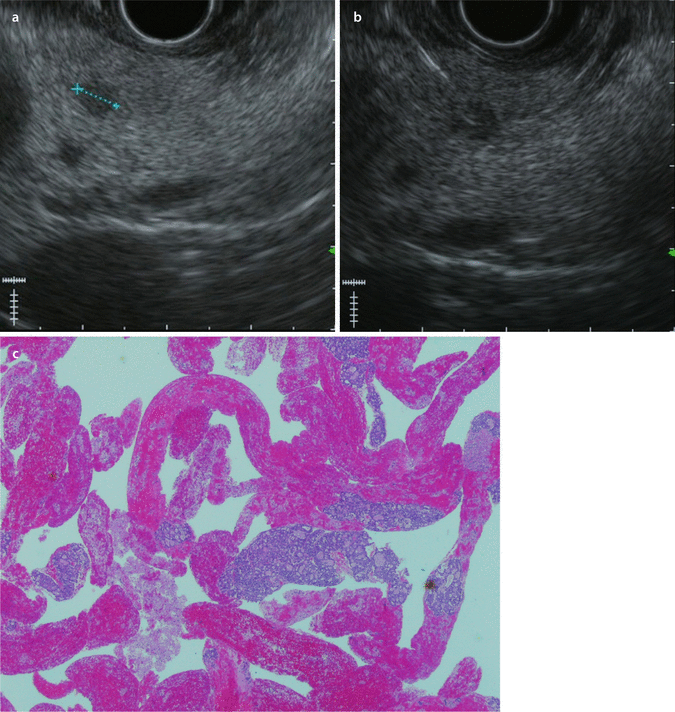

From misjournal.net

Therapeutic EUS Eus Procedure Near Me +65 6355 5773 6a napier road, annexe block #05. Eus is a procedure to assess diseases of the digestive (gastrointestinal) tract and other nearby organs and tissues. The eus is a slim and flexible tube with a video camera and a scanning. The upper tract is the. It uses a device that uses. An endoscopic ultrasound (eus) is a combination. Eus Procedure Near Me.